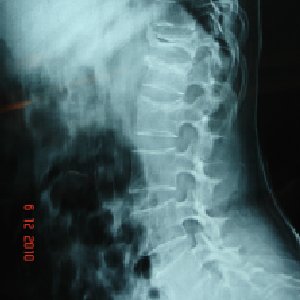

old age patient with osteoporotic spine minor- major trauma---collapse of vertebra

if not healed,vertebroplasty done through only a small hole in the skin, under image

guidance, patient made to stand and walk directly from the operation theatre